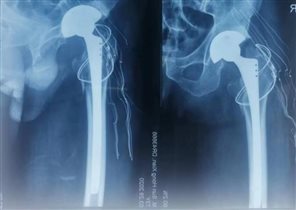

近年来,骨外科开展了我院的多项骨科首例手术,熟练开展髋关节置换手术、老年患者髋部骨折的髓内钉内固定术、胸腰椎体骨质疏松骨折的椎体成型手术、胸腰椎骨折微创内固定术等;在骨科多发伤、复杂骨折、老年患者骨质疏松治疗方面积累了丰富的经验。目前,骨外科成功完成胸腰椎椎体成型术年手术量70余例,可同时做三个椎体成型术,多数患者年龄在70岁以上,80岁以上患者占三分之一,所有患者术后腰背部疼痛均明显缓解。髋关节置换术已成为科室常规手术,髋关节置换年手术量50余例,膝关节置换、关节镜手术近年来手术患者均明显增加。科室能开展所有四肢骨折的手术治疗,年手术量达200余例。

近年来由于老龄患者明显增加,苏纯柱主任针对老年骨质疏松做了大量的工作,对于老龄骨质疏松骨折立足于防治结合,强调对于骨质疏松的早期干预治疗,指导患者规律治疗骨质疏松症。科室治疗的髋关节置换手术患者年龄最大92岁,术后一周患者自己步行出院。腰椎成型术最大年龄患者94岁,患者术后腰痛明显缓解,第二天即可下床活动。老年骨质疏松骨折的快速康复赢得了患者及家属的高度赞扬,提高了患者生活质量,所开展手术取得了患者的广泛认可,赢得了社会赞誉。

从事外科工作20余年、先后在山东省立医院、齐鲁医院、山东省千佛山医院进修学习,在临床工作中积累了丰富的经验。擅长骨科、普外科手术精细化、微创化操作,熟练开展四肢骨折、脊柱骨折的手术治疗,在全院率先开展了下肢骨折的MIPPO治疗、股骨近端髓内钉的闭合复位治疗、老年患者的骨质疏松骨折的椎体成形术、全髋关节置换术,熟练开展普外科常见病、多发病的手术治疗,广泛开展了腹腔镜下的阑尾切除术、腹股沟疝修补术、胆囊切除术、结直肠肿瘤切除术。在颈腰部、软组织疼痛治疗方面有深入研究,开展了肌肉软组织疼痛、膝关节疼痛的PRP治疗、针刀治疗、封闭注射等疗法,大大缓解了患者疼痛。在临床工作中坚守“医者仁心、患者至上”的宗旨、带领科室主动学习新技术、新方法,提高医疗技术、提高为患者服务的能力,开展了多例高难度复杂手术,为南部山区广大患者解除病痛,多次受到患者高度赞扬,赢得了患者的信任。